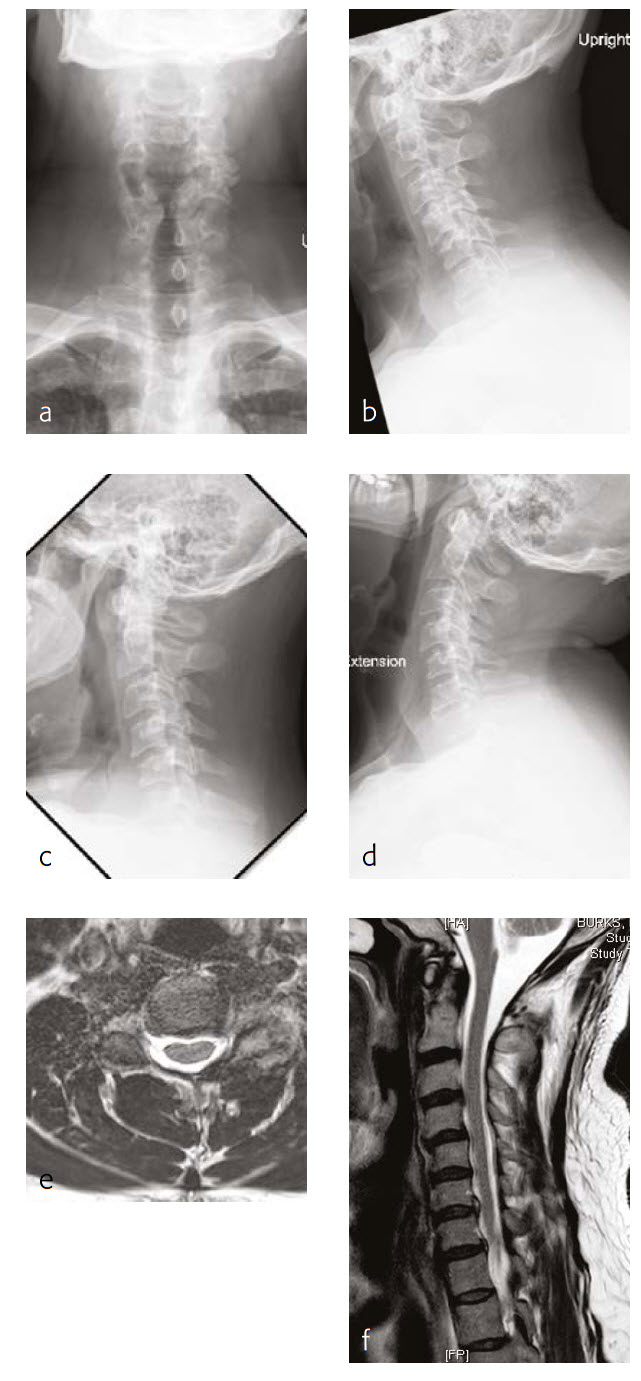

Case 1: Progressive shoulder and arm weakness with neck pain

A 56-year-old man, partly left-hand dominant partly right-hand dominant depending on the activity, presented with progressive left shoulder and arm weakness with pain radiating from his neck down to his left shoulder and an EMG documenting a left C5 radiculopathy (Fig 1).

The patient claimed a normal state of health until 5 weeks previous. This then began to backtrack to the neck and to develop weakness in his left arm to the biceps and deltoid. On examination, the patient had 4/5 deltoid and biceps strength on the left and decreased sensation along his lateral shoulder.

The patient showed normal lordosis in his extension x-rays. He has approximately 2 mm of anterolisthesis of C4 on C5 in his extension on his flexion x-ray. This increases to approximately 56 mm and persists in his normal upright film with again some component of spondylolisthesis at that level.

The patient's earlier MRI shows severe left-sided C4-C5 foraminal stenosis and multilevel disc degeneration with very mild central narrowing at C3-C4, C6- C7, and C7-T1. He also has a small right paracentral disc herniation at C6-C7.

The new MRI of the C4-C5 showed mild uncovering of the disc posteriorly due to grade 1 anterolisthesis. There is also mild left facet arthropathy with left uncovertebral joint osteophytes resulting in moderate left neural foraminal narrowing. The right neural foramen is adequately patent.

Follow-up (4 months)

At the patient follow-up at 4 months postoperative, he described complete resolution of left upper extremity pain (Fig 2). He was also happy with his left upper extremity strength and was extremely pleased with his progress. He continued to have no left upper extremity pain. He also believed that he had made significant progress in terms of his left upper extremity range-of-motion and strength.